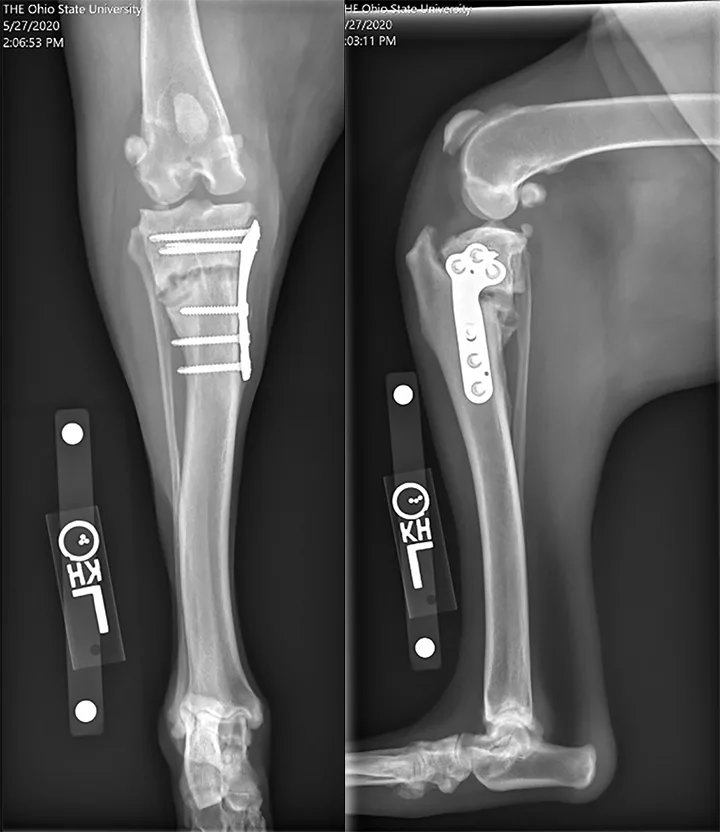

Radiographs from an 8-year-old spayed Rottweiler that underwent TPLO and was diagnosed with a superficial SSI 2 weeks postoperatively at another hospital. The SSI was treated with a 10-day course of antibiotics. The dog was presented to The Ohio State University Veterinary Hospital 6 weeks after surgery for recurrent lameness; the incision was healed, but osteomyelitis was confirmed on radiographs and fine-needle aspirate and cytology. Culture-based antibiotics were prescribed, but the infection did not resolve, the lameness was persistent, and the osteotomy became a nonunion. The patient was euthanized after developing a T3-L3 myelopathy suspected to be related to systemic infection.

Residual Instability

Cranial-caudal stifle instability is present postoperatively in one-third of TPLO-treated patients.14 Though the majority of dogs with postoperative instability are nonclinical, even nonclinical residual instability may result in a reduced long-term outcome. A more severe instability known as pivot shift, which involves cranial tibial subluxation coupled with a sudden lateral motion of the stifle during weight bearing, occurs in up to 3% of cases.7,12 The cause of residual instability has been hypothesized to be related to meniscectomy (or meniscal release) or incomplete plateau leveling.12,14 Incorrect osteotomy position (eg, osteotomy is positioned distally; Figure 3) or plateau rock-back can affect success in achieving or maintaining plateau leveling and therefore may affect stifle stability.1 In some cases, stifle instability after TPLO (including pivot shift) may resolve with time,8 likely due to improved muscular strength, which may support the hypothesis that some degree of instability can occur due to muscle weakness and further support the recommendation for postoperative physical therapy.

Featured Image

Figure 3

Immediate postoperative radiographs from a 2-year-old spayed medium-size crossbreed dog showing an inappropriately distally positioned TPLO. Distalizing the TPLO reduces the leveling achieved with planned rotation, leaves a narrow tibial crest (arrow), and positions the osteotomy in diaphyseal bone (slower to heal than metaphyseal bone). Also notable is the cranial position of the distal jig pin hole, which may predispose the patient to tibial diaphyseal fracture. This osteotomy position can be compared with that shown in Figure 4, in which the osteotomy position and resultant crest shape are appropriate.